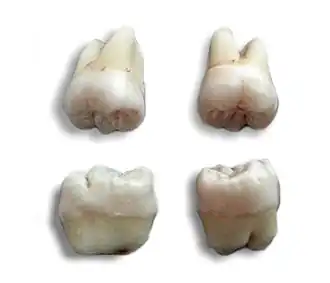

Tooth morphology

The morphology of wisdom teeth can be variable.

Maxillary (upper) third molars commonly have a triangular crown with a deep central fossa from which multiple irregular fissures originate. Their roots are commonly fused together and can be irregular in shape.

Mandibular (lower) third molars are the smallest molar teeth in the permanent dentition. The crown usually takes on a rounded rectangular shape that features four or five cusps with an irregular fissure pattern. Roots are greatly reduced in size and can be fused together.[13]